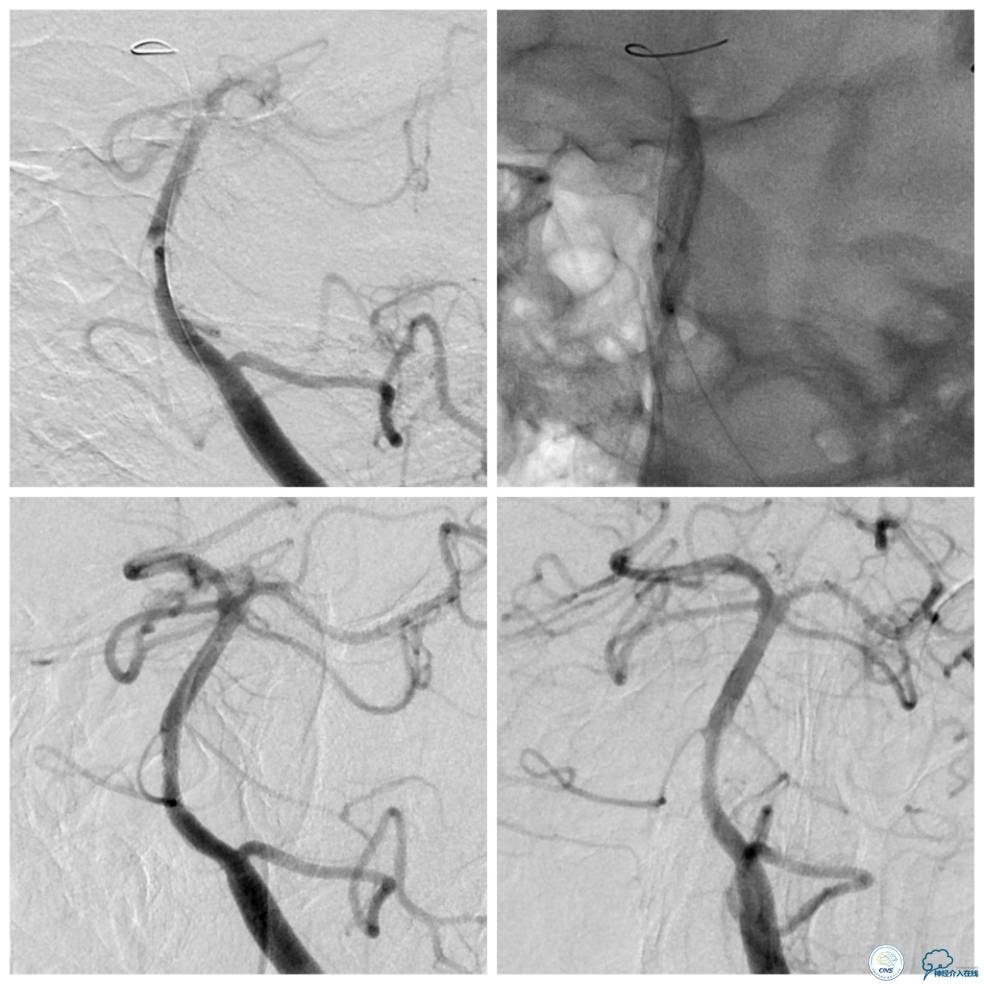

遂换用Traxcess微导丝(0.014″200cm)+Echelon-10微导管越过狭窄段后,重新交换Transend微导丝至右大脑后动脉P2段,Gateway球囊(2.0mm×9mm)扩张后,放置Apollo支架(2.5 mm×13mm)至狭窄段,球扩释放后支架贴壁良好,残余狭窄约15%,前向血流TICI3级(图8)。

图8

1.本例基底动脉“蜂巢样”狭窄形成与原重度狭窄的斑块内容物脱落有关,形成类似斑块掀起的改变,该狭窄如果对血流动力学存在影响,会产生低动力缺血症状。

2.本例治疗过程难点在于微导丝越过病变,导丝操控要轻柔,避免大幅度旋转动作,防止形成医源性夹层。

3.具体材料选择感觉Traxcess微导丝过类似病变能力更强一点。

4. 管腔内的充盈缺损征象,有时类似血管开窗,高分辨核磁可能有助于鉴别。